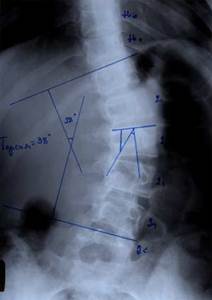

До сих пор в ортопедии принято множество методик измерения угла искривления позвоночника, и, соответственно, множество различных классификаций с разными величинами углов в градусах. Измеряется искривление так: на рентгенограмме надо провести несколько прямых линий между позвонками, а затем измерить углы между ними. В нашей стране наиболее распространена классификация, предложенная В.Д. Чаклиным. В иностранных научных источниках чаще приводится метод Дж. Кобба. Суть его заключается в следующем: на рентгеновском снимке позвоночника врач измеряет S-образное двойное искривление. В верхнем участке искривления с помощью линейки проводят две горизонтальные линии: одна над верхним позвонком, от которого идет кривизна, другая - над нижним. Если провести еще две линии, идущие перпендикулярно первым, образуется угол. Его и измеряют в градусах

Как видно, принцип измерения как у русского, так и американского профессора практически одинаковый. Разница в том, что по Чаклину, чем больше градусов, тем легче степень болезни, а по Коббу - наоборот.

Классификация выраженности сколиоза по В.Д. Чаклину (слева), по Лж. Коббу (справа) Степени тяжести сколиоза (углы искривления позвоночника, в градусах) Графический расчет на рентгенограмме: а - I степень; б - II степень; в - III степень; г - IV степень.

По В.Д. Чаклину

По Дж. Коббу

I степень 180 - 175 меньше 15

II степень 175-155 20-40

III степень 155-100 40-60

IV степень меньше 100 больше 60

Больной П-ко, 15 лет Поясничный сколиоз III степени  Результат оперативного лечения

При сколиозе IV степени с углом деформации в диапазоне от 51° до 70° коррекция составила от 79,2 до 84,8%. С углом от 71° дог 80° - 73,3 - 86,5%. С искривлением от 81° до 122° удалось достигнуть одномоментно коррекции в пределах 72,7 - 73,8%.